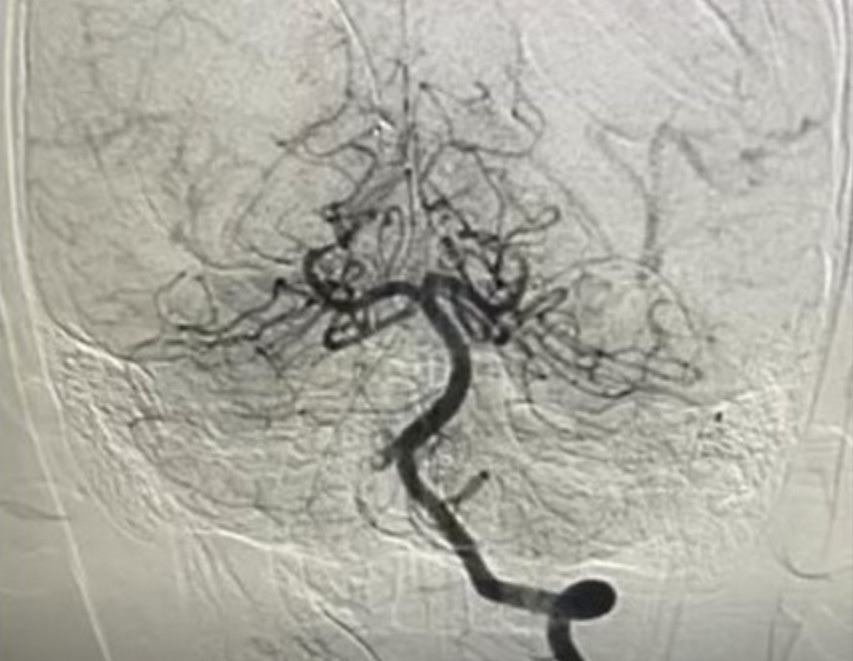

Hình ảnh chụp mạch máu xóa nền DSA xác định tình trạng nhồi máu não của bệnh nhi.

Tại Bệnh viện Nhi đồng Thành phố, bệnh nhi được chụp MRI não và cột sống cổ, ghi nhận nhồi máu não cấp vùng hành não, kèm huyết khối gần như tắc hoàn toàn động mạch đốt sống phải.

Ngay lập tức, các bác sĩ hội chẩn liên khoa, chỉ định chụp mạch máu kỹ thuật số xóa nền (DSA) và can thiệp nội mạch cấp cứu.

BS-CKII Trần Công Bảo Phụng cùng ê-kíp đã luồn ống thông theo đường động mạch đùi đến động mạch đốt sống, dùng thuốc tiêu sợi huyết tại chỗ kết hợp hút huyết khối, tái thông hoàn toàn mạch máu não cho bệnh nhi.